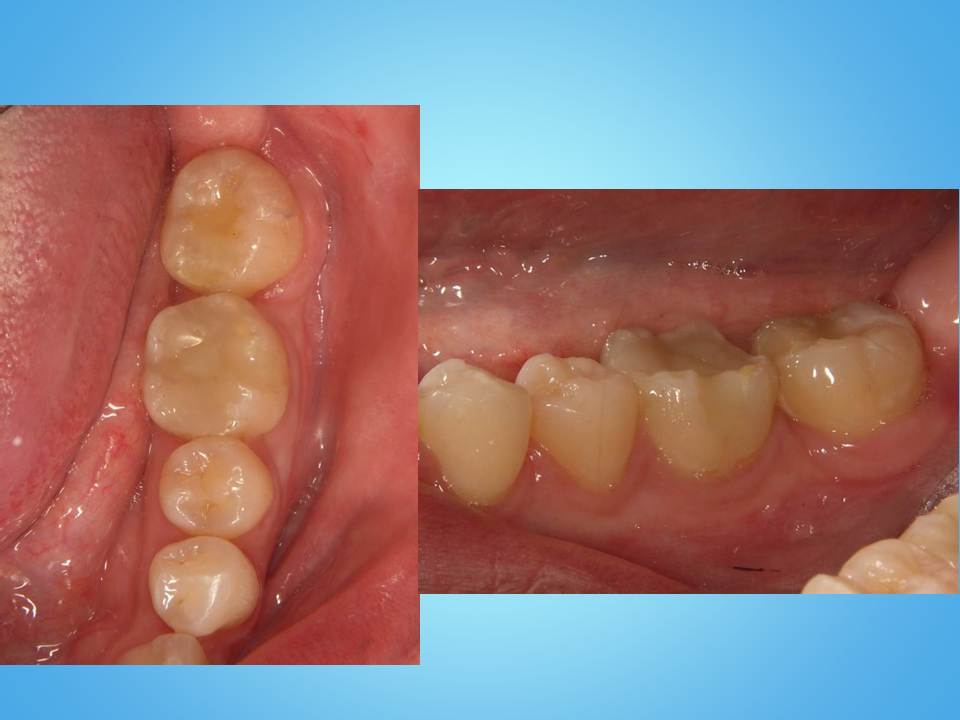

痛みは以上の治療で改善することができるのですが、修復するのにこのままの状態では治療することができません。

それは、かけけしまった部分が歯茎の内側まで入り込んでしまっているからです。

このような場合、かけてしまった部分を歯茎の外側まで出す必要があります。

その治療として有効な方法は矯正により歯を引っぱり出すエクストルージョン(歯根挺出)です。

矯正後に仮歯を入れた状態です。

かけてしまった部分を歯茎の外側まで出すことにより、仮歯を付けることができました。